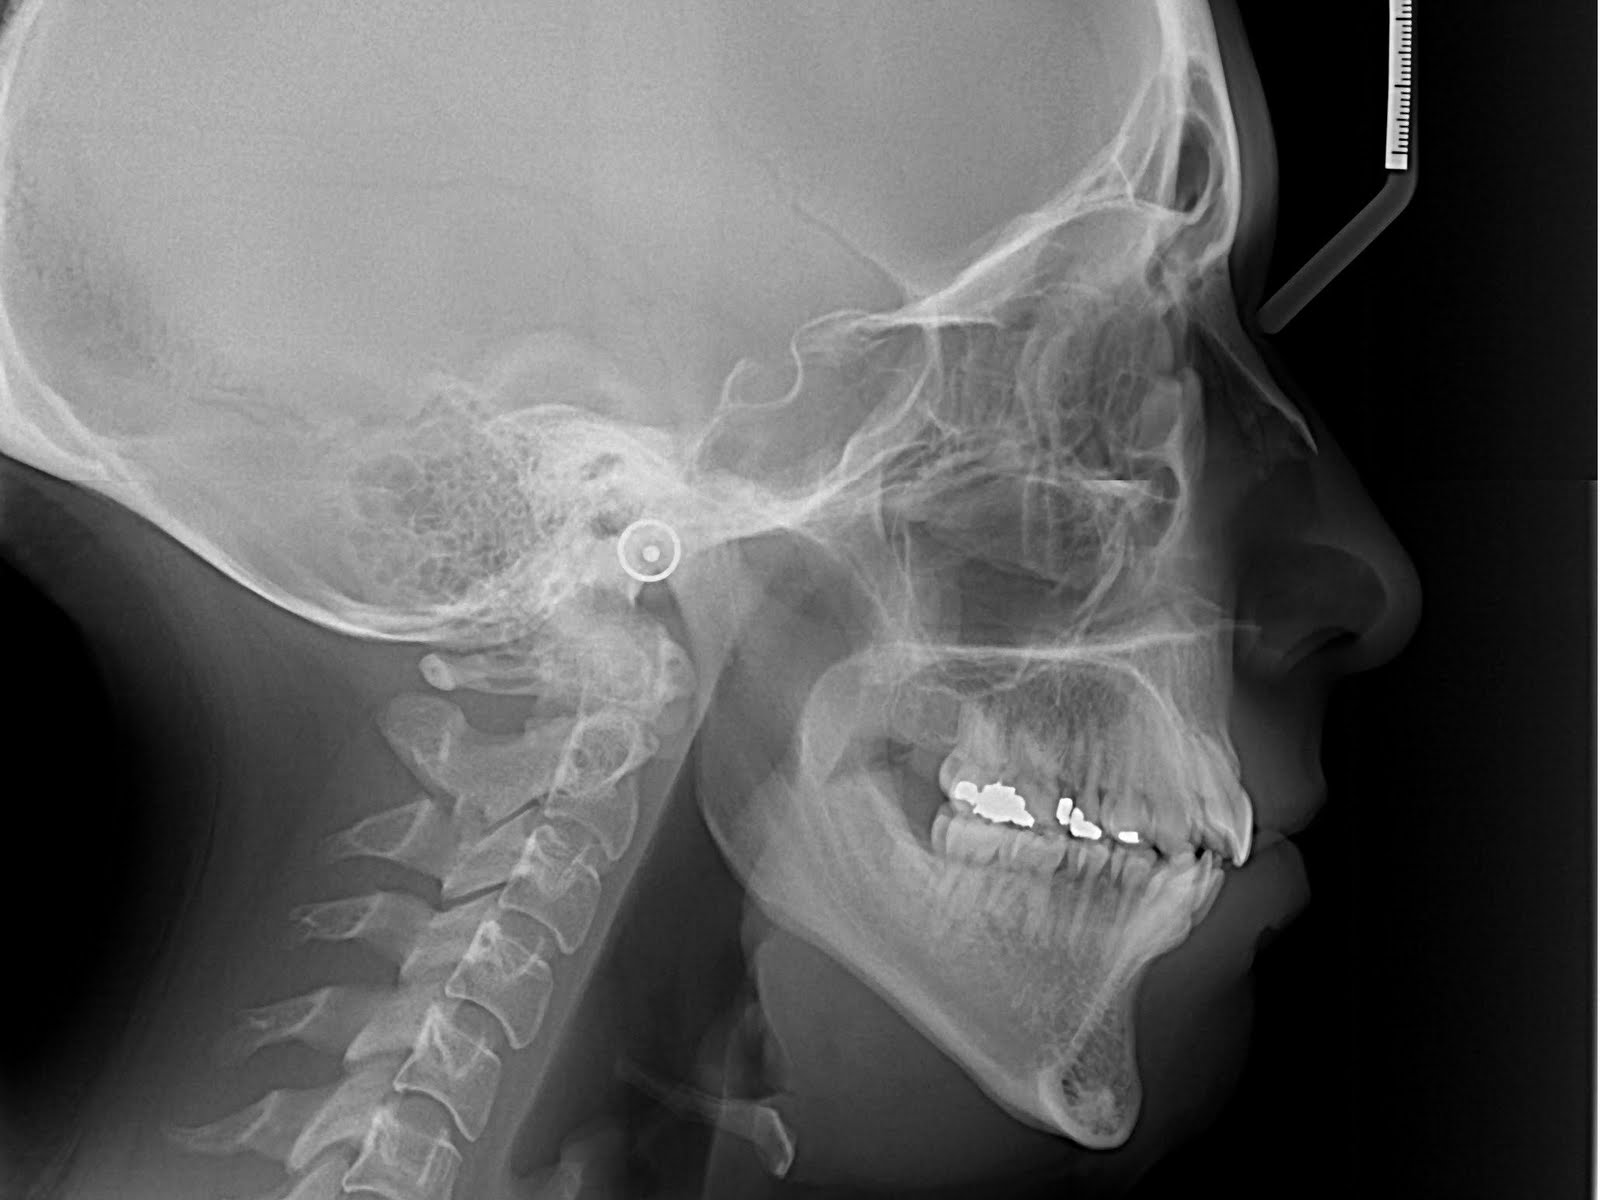

A look at Colby Covington's broken jaw Xray

Xray of Colby Covington's broken jaw reveals the extent of damage he Covington Jaw X Ray Colby covington has repeatedly denied that his bitter rival kamaru usman did not actually break his jaw at the ufc 245 main. Speaking to brett okamoto of espn mma, 'chaos' addressed the. It was widely reported that kamaru usman broke colby covington 's jaw during their ufc 245 main event clash in 2019. Covington Jaw X Ray.

Colby Covington Xray released and shows clear crack in broken jaw he Covington Jaw X Ray Colby covington has repeatedly denied that his bitter rival kamaru usman did not actually break his jaw at the ufc 245 main. It was widely reported that kamaru usman broke colby covington 's jaw during their ufc 245 main event clash in 2019. Speaking to brett okamoto of espn mma, 'chaos' addressed the. Covington Jaw X Ray.

Loudmouthed Colby Covington shows off Xray of brutally broken jaw Covington Jaw X Ray It was widely reported that kamaru usman broke colby covington 's jaw during their ufc 245 main event clash in 2019. Speaking to brett okamoto of espn mma, 'chaos' addressed the. Colby covington has repeatedly denied that his bitter rival kamaru usman did not actually break his jaw at the ufc 245 main. Covington Jaw X Ray.

Colby Covington Shows Off Grim XRay Of Broken Jaw After Being Smashed Covington Jaw X Ray Speaking to brett okamoto of espn mma, 'chaos' addressed the. Colby covington has repeatedly denied that his bitter rival kamaru usman did not actually break his jaw at the ufc 245 main. It was widely reported that kamaru usman broke colby covington 's jaw during their ufc 245 main event clash in 2019. Covington Jaw X Ray.